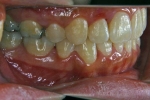

カテゴリー:ClassⅡ division 2 malocclusion (Overbite 5mm以上; 抜歯症例)

しかし、出題基準にも書いてあるように、このケースは欧米の白人によく見られるケースで、東洋人にはきわめて稀である。そこで類似ケースとして過蓋咬合(かがいこうごう)のケースを代替えとして認めるという配慮をしている。過蓋咬合とは非常に強く深く咬んでいる状態を言う。Overbiteとは前歯の垂直的な重なり具合を示す数値で、5mm以上だと上の前歯が下の前歯をほとんど覆い尽くしている感じになるので、前から見ると下の前歯はほとんど見えない状態になる。こういう状態が典型的な過蓋咬合である。典型的なclassⅡ,division 2のケースは過蓋咬合を合併している。

| 初診時